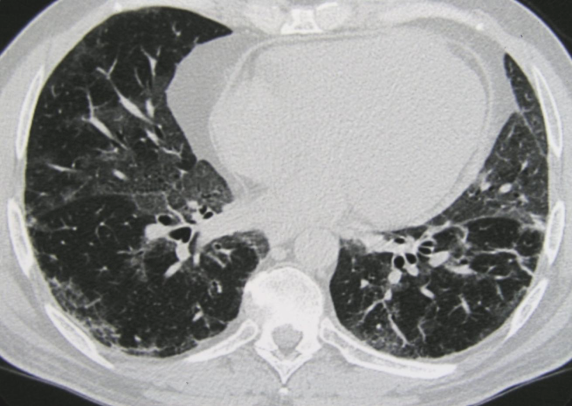

病例:这位患者表现为马赛克灌注(Mosaic perfusion),与马赛克影的相同点是都出现在吸气相CT,而马赛克灌注是指的在正常密度的肺脏下,吸气相CT看到了一些低密度区,这些低密度区这提示血管或气道疾病,提示血管减少、气体陷闭。

ero为什么不显示叶俏教授:HRCT是发现和鉴别「过敏性肺炎」的重要环节,何种表现指向预后不良?使患者发病的危害因素躲在哪些环境中?_https://www.jmylbn.com_新闻资讯_第34张

同时我们看到患者还伴有小叶中央型的磨玻璃样结节,可见吸气相(下图左)和呼气相(下图右)是有明显差别的。

ero为什么不显示叶俏教授:HRCT是发现和鉴别「过敏性肺炎」的重要环节,何种表现指向预后不良?使患者发病的危害因素躲在哪些环境中?_https://www.jmylbn.com_新闻资讯_第35张

三种密度征(Three density pattern)里的三个区域分别是:高密度区提示磨玻璃影子,低密度区提示小气道疾病所累及的肺脏出现了气体陷闭的表现,还有一些正常的肺脏。

当出现三种密度征的时候,结合临床,能够高度提示这个患者是 HP。

这位慢性纤维化型过敏性肺炎患者就可以看到三种密度征、磨玻璃影、网格影、牵拉性支气管扩张,没有蜂窝。